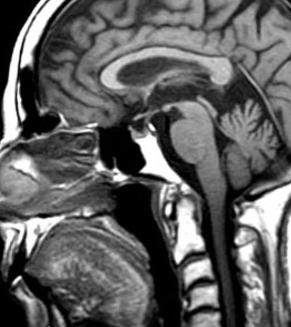

Physicians at UPMC in Pittsburgh developed new technique around 2010. Using a small endoscope, through the nose, then a small catheter through the back of the nasopharynx ( nose/mouth ) they removed ( via tiny drill ) most of C1 and C2. Quite risky being that close to brain stem. No small complications, sort of an all or nothing thing. This is me 2 weeks post surgery.

MRI 3 months post surgery -   Blood resolved. Brain stem relaxed and expanded forward by almost 4 mm which might as well be a football field (in places) in the brain for those who are not familiar with brain anatomy.